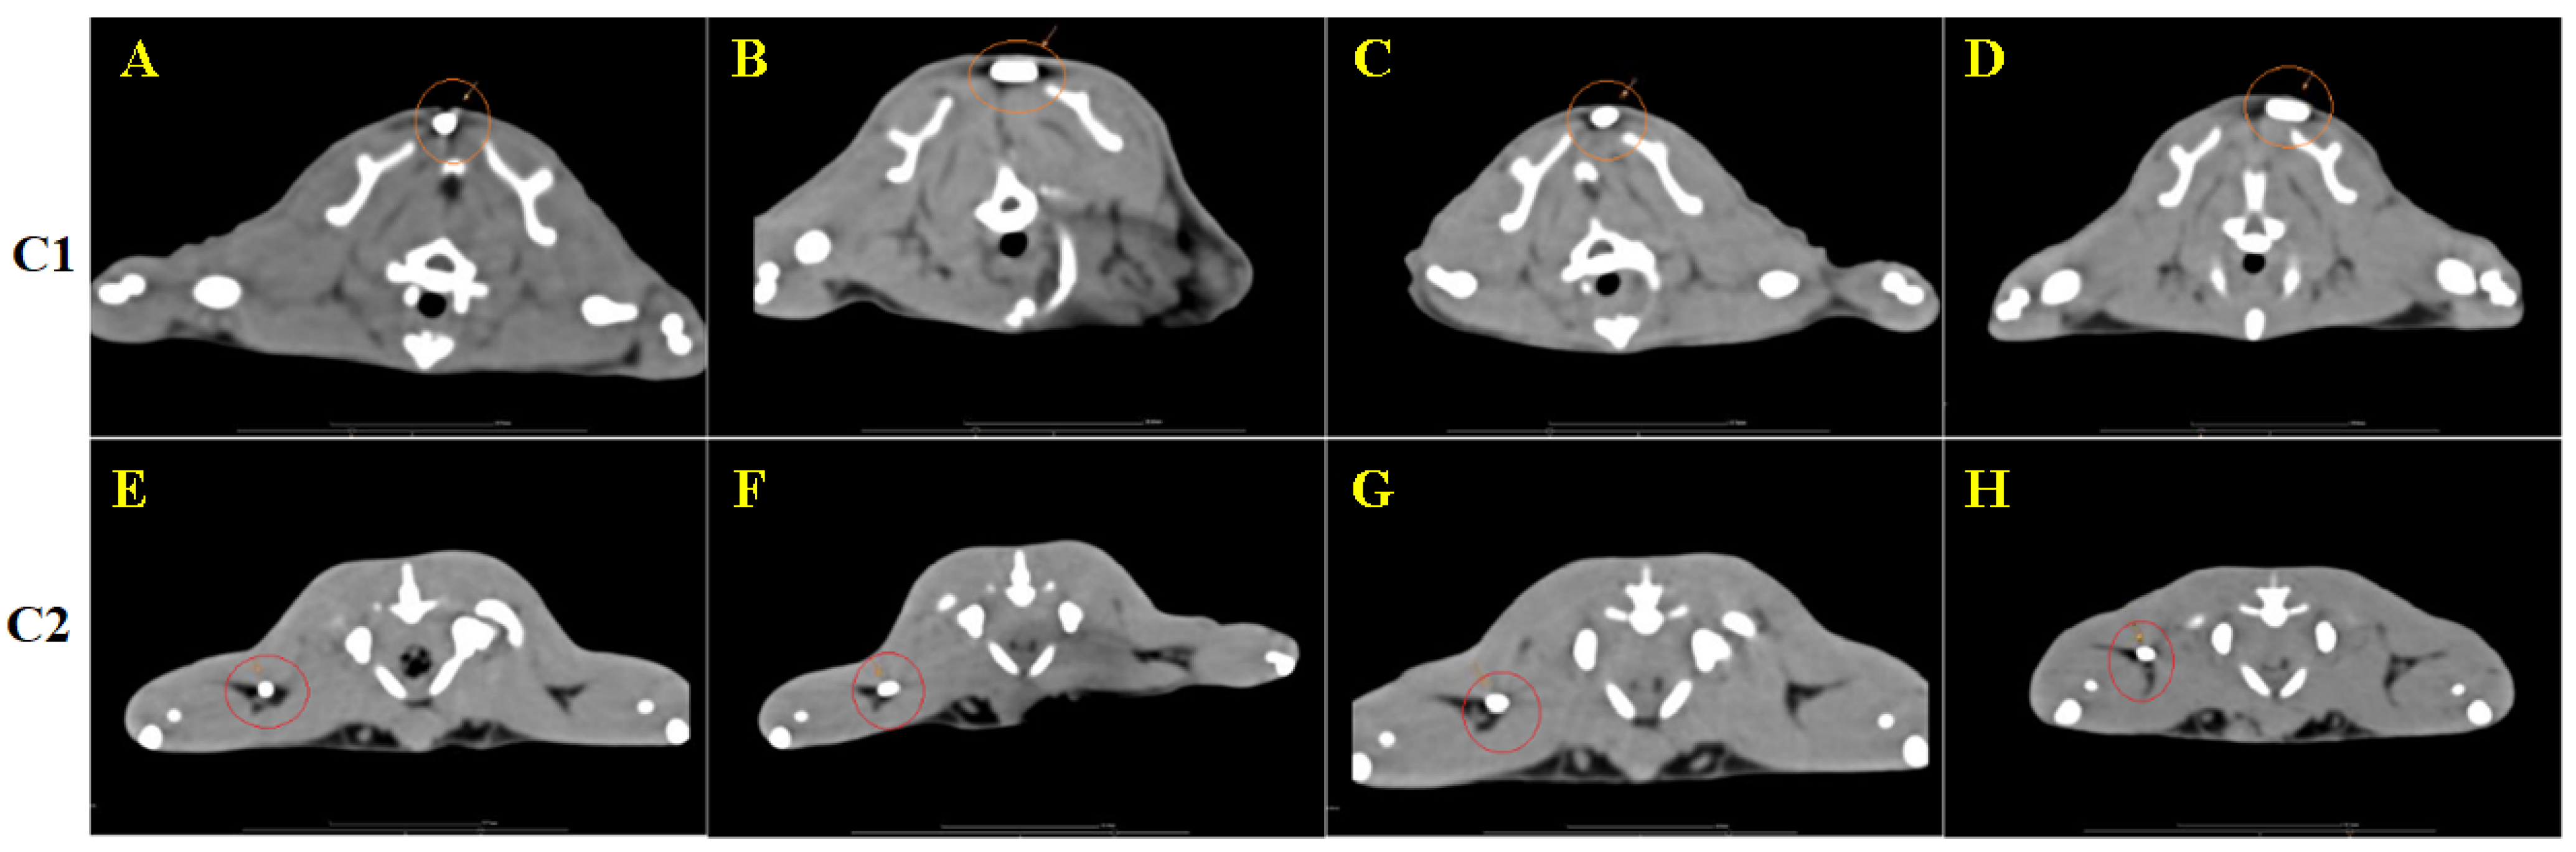

3.4. CT Image Findings